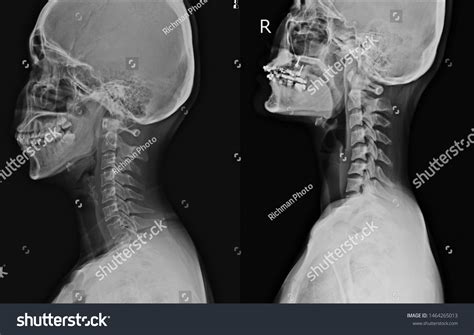

Receiving medical imaging results can often feel overwhelming, especially when you are unsure what the terminology implies for your long-term health. A normal neck X-ray, medically referred to as a cervical spine radiograph, is a common diagnostic tool used by healthcare providers to visualize the seven vertebrae that make up your neck. If your report indicates that your findings are within normal limits, it typically means the radiologist did not detect any fractures, significant misalignment, or severe degenerative changes at the time of the scan. Understanding what this diagnostic baseline represents is crucial for anyone navigating neck pain, stiffness, or post-injury evaluation.

The human neck is a complex structure consisting of seven vertebrae (C1 through C7), discs, muscles, ligaments, and nerves. A normal neck X-ray focuses primarily on the bony structures. Because X-rays are excellent at capturing high-density tissues, they provide a clear view of the vertebrae, the spaces between them (which house the discs), and the alignment of the spine.

During a standard evaluation, a radiologist looks for several key markers to determine if the anatomy is "normal." These include:

• Cervical Lordosis: The natural inward curvature of the neck that helps support the weight of the head.

• Vertebral Integrity: Checking for the absence of cracks, chips, or compression fractures.

• Disc Space Height: Ensuring the spaces between vertebrae are uniform and not abnormally narrowed, which could indicate disc degeneration.

• Alignment: Verifying that the vertebrae are stacked correctly without forward or backward slipping (spondylolisthesis).